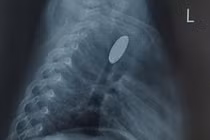

Đối với triệu chứng đau âm ỉ quanh vùng gót chân trái, kết quả chụp Xquang cho thấy, hình ảnh gai xương gót chân trái - nghi ngờ viêm cân gan chân mạn tính.

Xquang thấy hình ảnh gai xương gót bàn chân trái/Ảnh BV medlatec